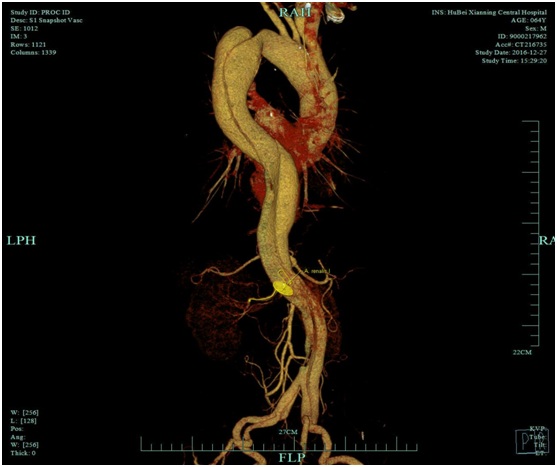

血管外科:胸腹主动脉夹层支架植入术

近日,血管外科在外请专家指导下成功行胸腹主动脉夹层覆膜支架植入术2例,其中一例患者已顺利出院,结束了我院治疗胸腹主动脉夹层需要转院的历史,血管外科将进一步发展血管外科腔内治疗技术和结合手术治疗的血管杂交技术。